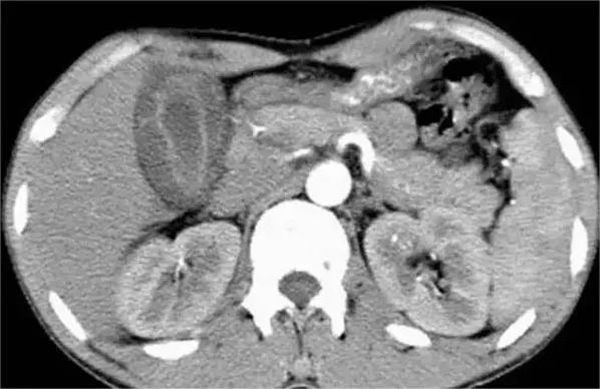

这是一种比较危险的疾病,可能引起突发性腹部剧烈疼痛,同时伴有恶心、呕吐等症状。腹部压痛轻,肠鸣音活跃,随着病变的进展,腹胀逐渐加剧,出现腹膜炎体征,肠鸣音消失,可有血便,并迅速出现休克。X线腹部平片可见肠管扩张,气液平面,但X线腹部平片也可无异常发现。需与肠扭转、肠套叠或急性出血性肠炎等鉴别。